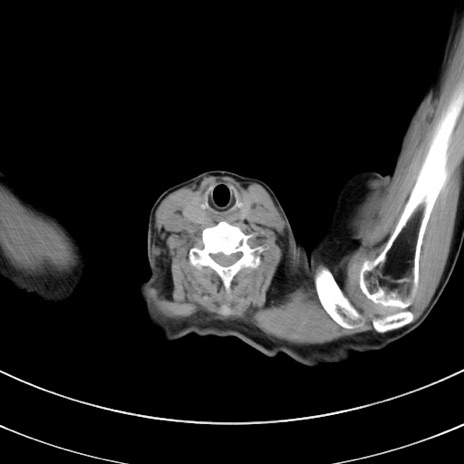

症例33(横断像)

【症例】70歳代 女性

【主訴】心窩部痛

【現病歴】延髄病変の精査・加療にて神経内科入院中。本日より心窩部痛あり。

【既往歴】虫垂炎

【身体所見】右下腹部を中心に圧痛と反跳痛あり。

【データ】WBC 10900、CRP 0.02